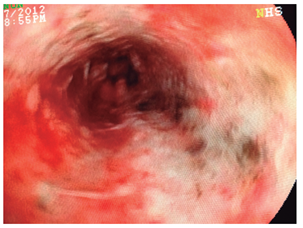

Mujer de 79 años, que consulta por urgencias por melanemesis y alteración de la conciencia. Como antecedente presentaba meningioma resecado, con síndrome convulsivo secundario, hipertensión arterial no controlada y enfermedad pulmonar obstructiva crónica. En los exámenes presentaba leucocitosis con neutrofilia (89 %); creatinina de 1,84 mg/dL, hipocloremia (92 mEq/L) e hiponatremia (129 mEq/L). La endoscopia mostró esfacelo del epitelio esofágico en los dos tercios inferiores y sangrado difuso en la capa (Figuras 1, 2, 3 y 4), sin cambios en el calibre. Se desconoce su evolución y su desenlace.

Los hallazgos endoscópicos son diversos y requieren que se descarten otras etiologías que producen alteraciones similares, como la ingestión de cáusticos, otros tóxicos o carbón, infecciones, radioterapia o melanoma metastásico, entre otros 3,10. Los hallazgos pueden ir desde membranas blanquecinas, que al removerlas dejan una mucosa grisácea o negruzca, hasta necrosis difusa con exudados amarillentos adherentes, ulceración en la mayoría y aspecto negruzco o grisáceo, demarcado por la unión gastroesofágica, con región cardial de aspecto usual, como se describen en nuestros casos. El espectro de lesiones asociadas es amplio, como hemorragia gástrica o duodenal, ulceraciones y perforaciones, representadas en la casuística general con úlceras duodenales (10; 4 %), gástricas (2; 1 %), necrosis isquémica duodenal (2; 1%); sangrado activo (4; 2 %), perforación esofágica (3; 1,3 %) y duodenal (1; 0,5 %) (Tabla 1).